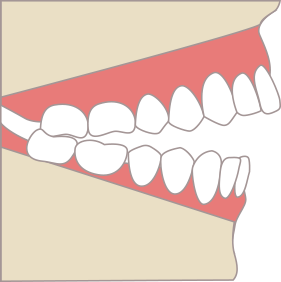

前歯がかみ合っていない開咬という状態

開咬という前歯、犬歯がかみ合っていない状態だと、先ほどの八重歯と同じく、前歯や犬歯が機能せず、それらの機能を奥歯で一挙に代償します。そのため、奥歯の使用頻度が高くなり、奥歯の寿命が縮んでしまいます。そのため、矯正治療を行い、前歯の噛ませて機能回復することが重要になります。

開校(かいこう)に対するアライナー治療の優位性

開咬(かいこう)の

状態

奥歯で噛んでも前歯が開いてしまう状態。

前歯で食べ物を噛み切れない。

アライナーによる

臼歯の圧下(あっか)

アライナーの厚みが奥歯に「染み込む力」を加え、開咬の原因となる奥歯の高さを低くする。

治療効果とメリット

奥歯が圧下されることで下顎が回転し、前歯が閉じる。

透明で目立ちにくく、取り外せるため衛生的。